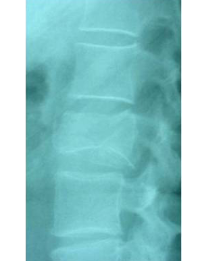

Clinical case example of a lumbar vertebral body resection (corpectomy) and reconstruction of a burst fracture at level L4.

Vertebral body resection (corpectomy) and reconstruction of complex vertebral and burst fractures

Severe vertebral body fractures, i.e. conminute and burst fractures, may require a partial vertebral body resection (corpectomy) and reconstruction with an expandable vertebral body cage. Especially severe fracture cases are also those with a bone fragment moving into the spinal canal that compresses on neural structures, such as the spinal cord and causes spinal canal stenosis. Corpectomy allows to resect most of the fractured body, including the bone fragments pushing on the nerves and intruding into the spinal canal. The vertebral body reconstruction is usually rounded up with a posterior augmented instrumented fusion of the adjacent levels to the fracture. All of this allows a proper healing of the fracture and the patient to recover without pain.